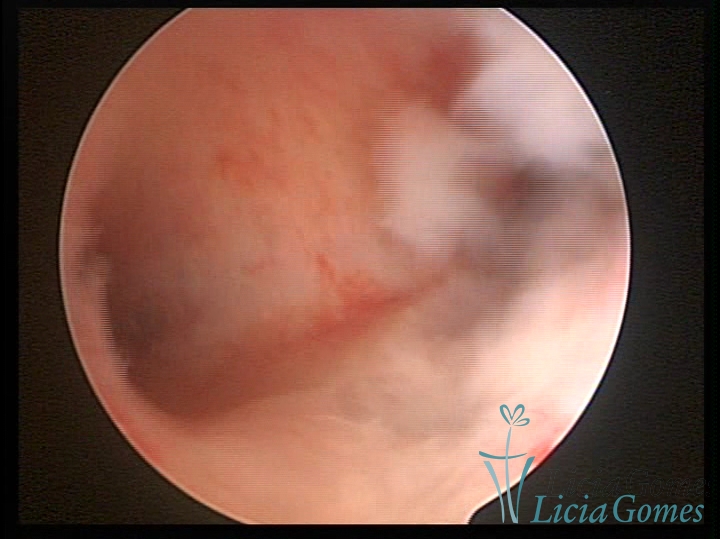

Unicornuate uterus

It presents a tubular cavity with an impaired intracavitary space, resembling the shape of a banana, whose the narrowest edge contains the tubal ostium. The endometrium is compatible with the menstrual cycle and the cervical canal is normal, in structure and trophism.